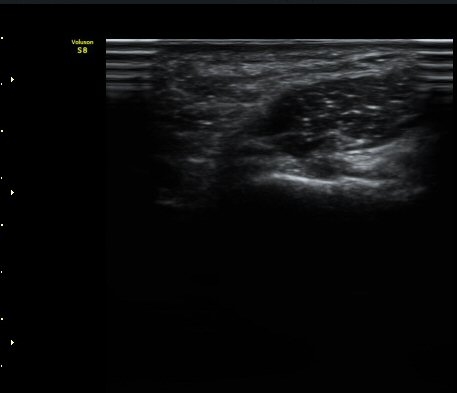

ŽÃËÀÚ¸¦ Á» ´õ ³»ÃøÀ¸·Î °æ»ç¸¦ ÁÖ¾î °¥°í¸®»À °í¸®ÀÇ Ãø¸éºÎ¸¦ °üÂûÇÏ´Ï °¥°í¸®»À °í¸®ÀÇ

ÇÇÁú°ñ ¿¬°á¼º ¼Ò½Ç(°ñÀý)°ú ±¹¼ÒÀû Àú¿¡ÄÚ ºÎÁ¾ÀÌ °üÂûµÇ°í Àú¿¡ÄÚ ºÎÁ¾ ¿ÜÃø¿¡¼­ ö°ñ½Å°æ

½ÉºÎ°¡Áö°¡ °üÂûµÈ´Ù(±×¸² 2, 3, 4,).